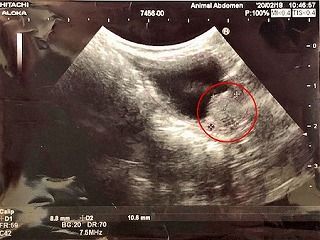

一番最初のレントゲン写真(当店に来る前)

この後「Pet水素」とアガリクス入りフード「AGARx」を使用開始

3週間後

そして...おととい再々度レントゲンを撮ったら

ガン巣が見えなくなっていた のだそうです